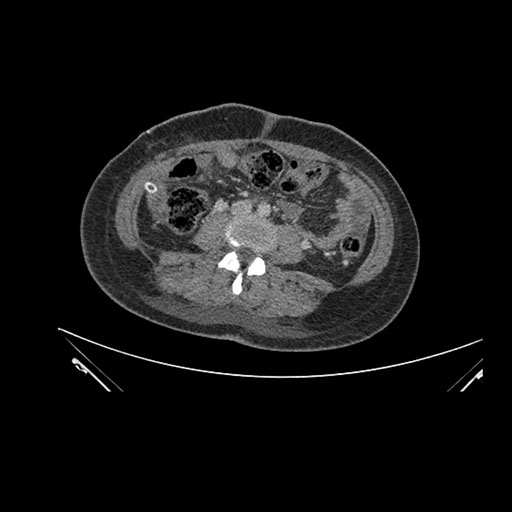

Imaging Analysis

Look through the patient's CT scan to identify any areas of concern for the necessary procedure.

Axial Arterial

Axial Venous

Based on initial findings, which issue(s) would you be most concerned about?